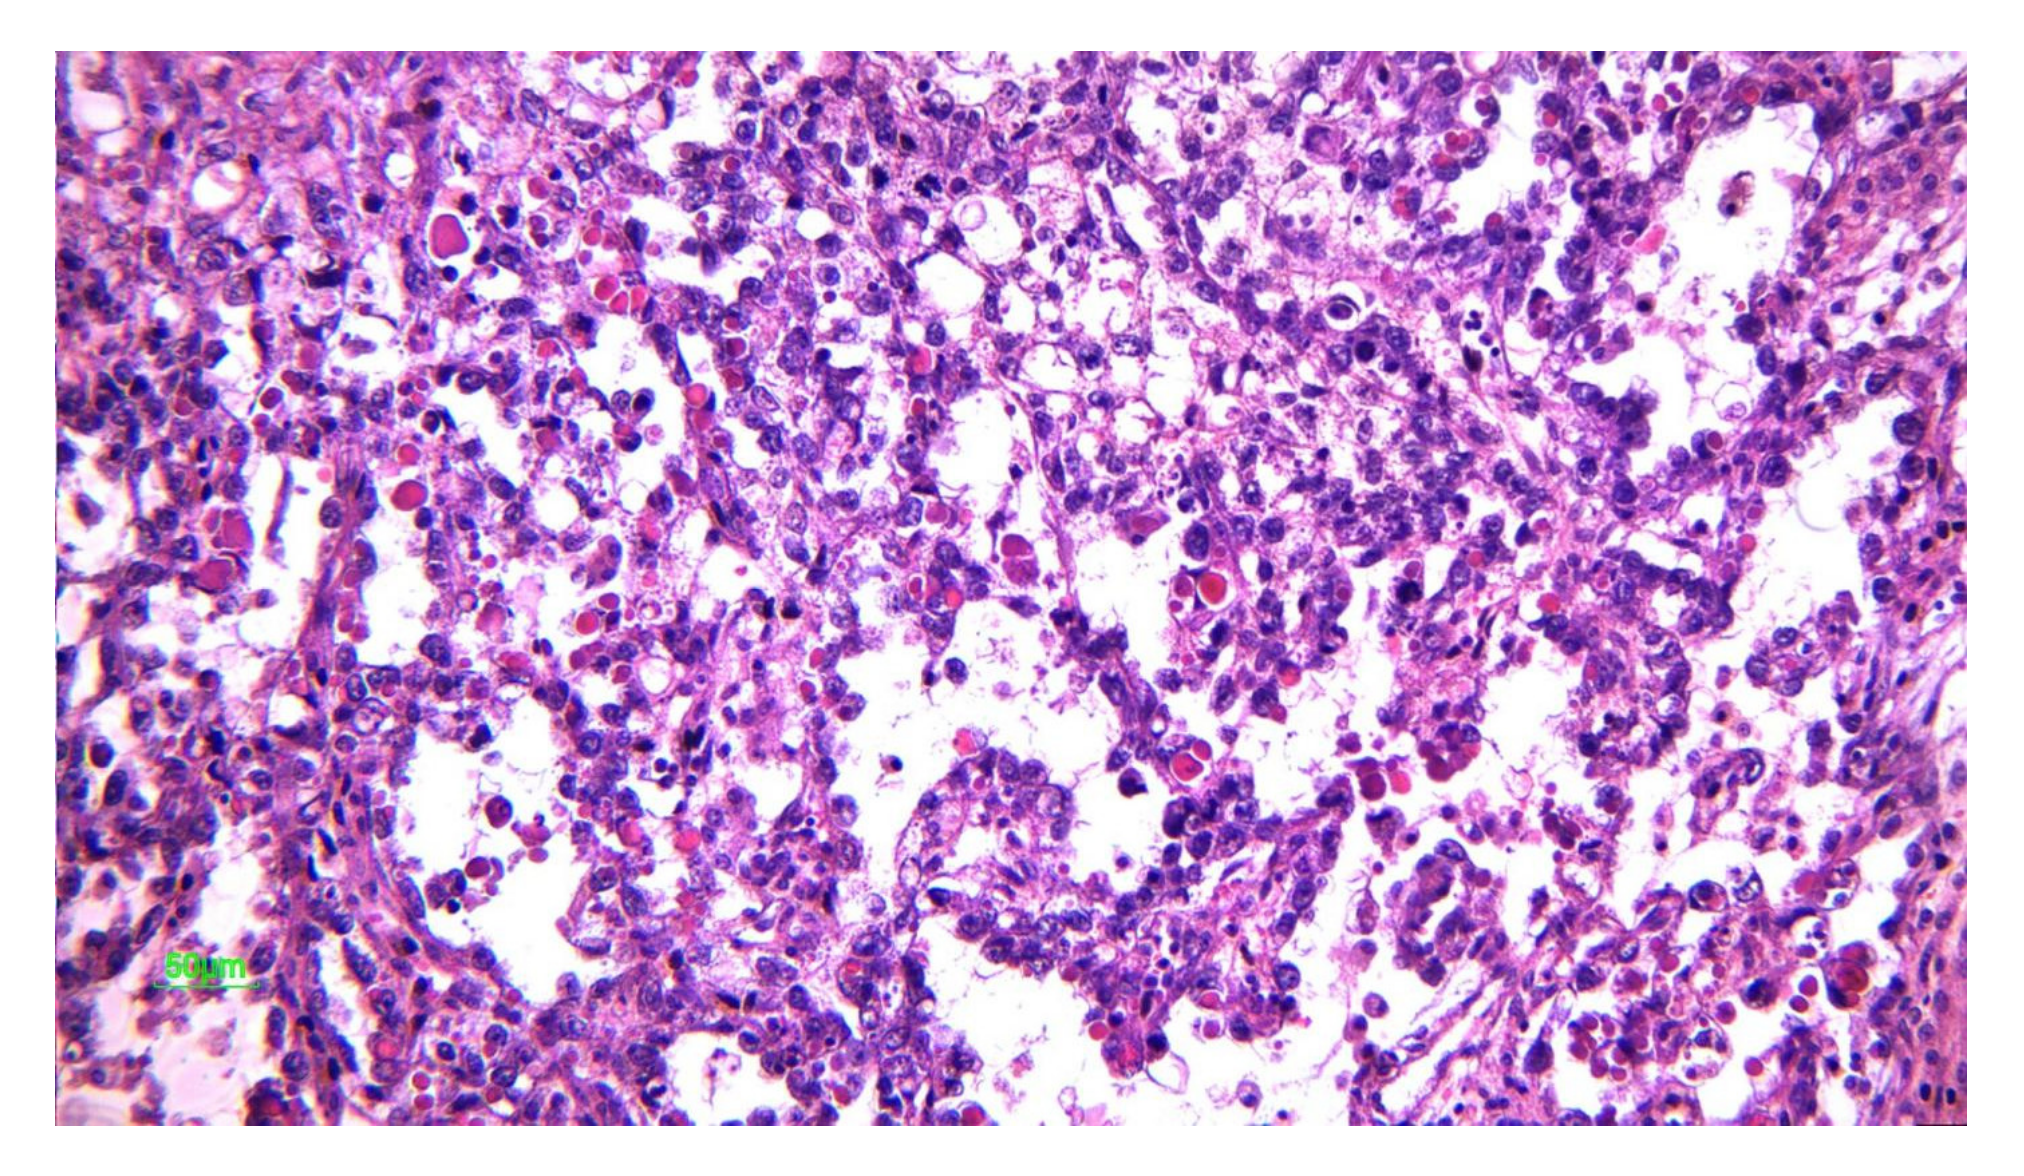

2.1.2. Microscopic Features

2.3.2. Microscopic Features

2.5.2. Microscopic Features